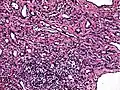

Micrograph of a kaposiform hemangioendothelioma with "glomeruloid" nodules of endothelial cells.

• Kaposiform hemangioendothelioma (also known as "Infantile kaposiform hemangioendothelioma"[3]) is an uncommon vascular tumor, first described by Niedt, Greco, et al. (Hemangioma with Kaposi's sarcoma-like features: report of two cases.(Niedt GW, Greco MA, Wieczorek R, Blanc WA, Knowles DM 2nd. that affects infants and young children, with rare cases having also been reported in adults. Pediatr Pathol. 1989;9(5):567-75.)[2]: 596 [3]: 1782